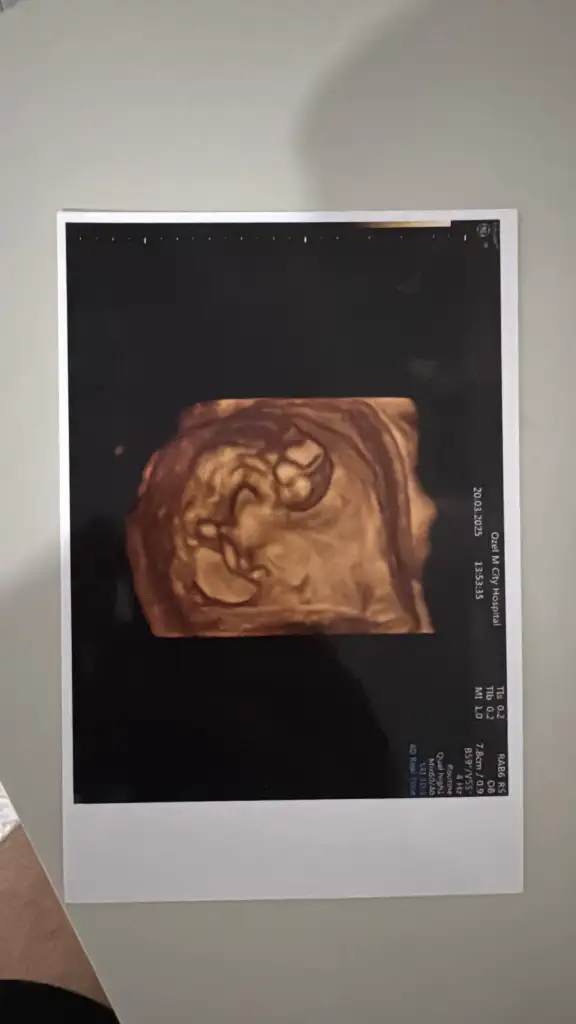

benimkine de yorum yapar mısınızz çok meraktayım en son 12.haftada gittik şu an 14+2 deyizNub teorisine göre erkek

3d görüntü ile tahmin yapamıyorumbenimkine de yorum yapar mısınızz çok meraktayım en son 12.haftada gittik şu an 14+2 deyiz